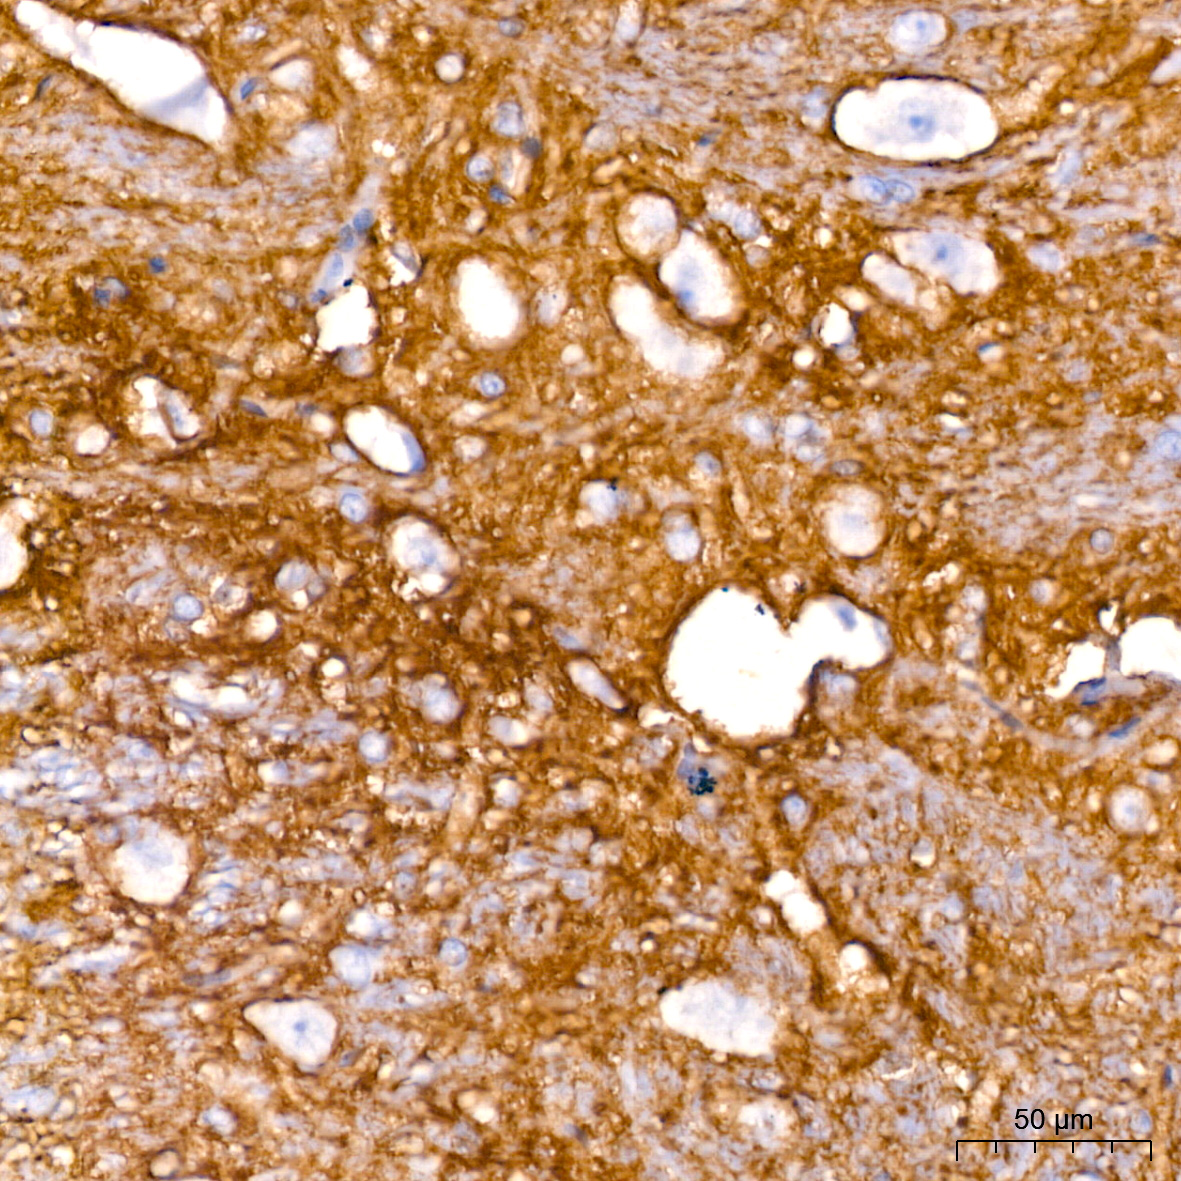

IHC

神经传递是神经化学信号从一个神经元传递到相邻神经元的过程。神经递质由突触前神经元释放穿越突触间隙,然后结合并激活突触后神经元上的受体,有许多不同类型的神经递质,包括乙酰胆碱、氨基酸(天冬酰胺、GABA、谷氨酸和甘氨酸)、单胺(多巴胺、组胺、肾上腺素和去甲肾上腺素)和各种神经肽。

神经传递是通过神经元之间的电信号和化学信号来进行信息传递。电信号通过动作电位沿神经元轴突传播,而化学信号则通过神经递质在突触间隙中传递。

这是最常见的神经传递方式,主要通过突触间隙释放和接收神经递质来实现。下表为常见的神经递质: